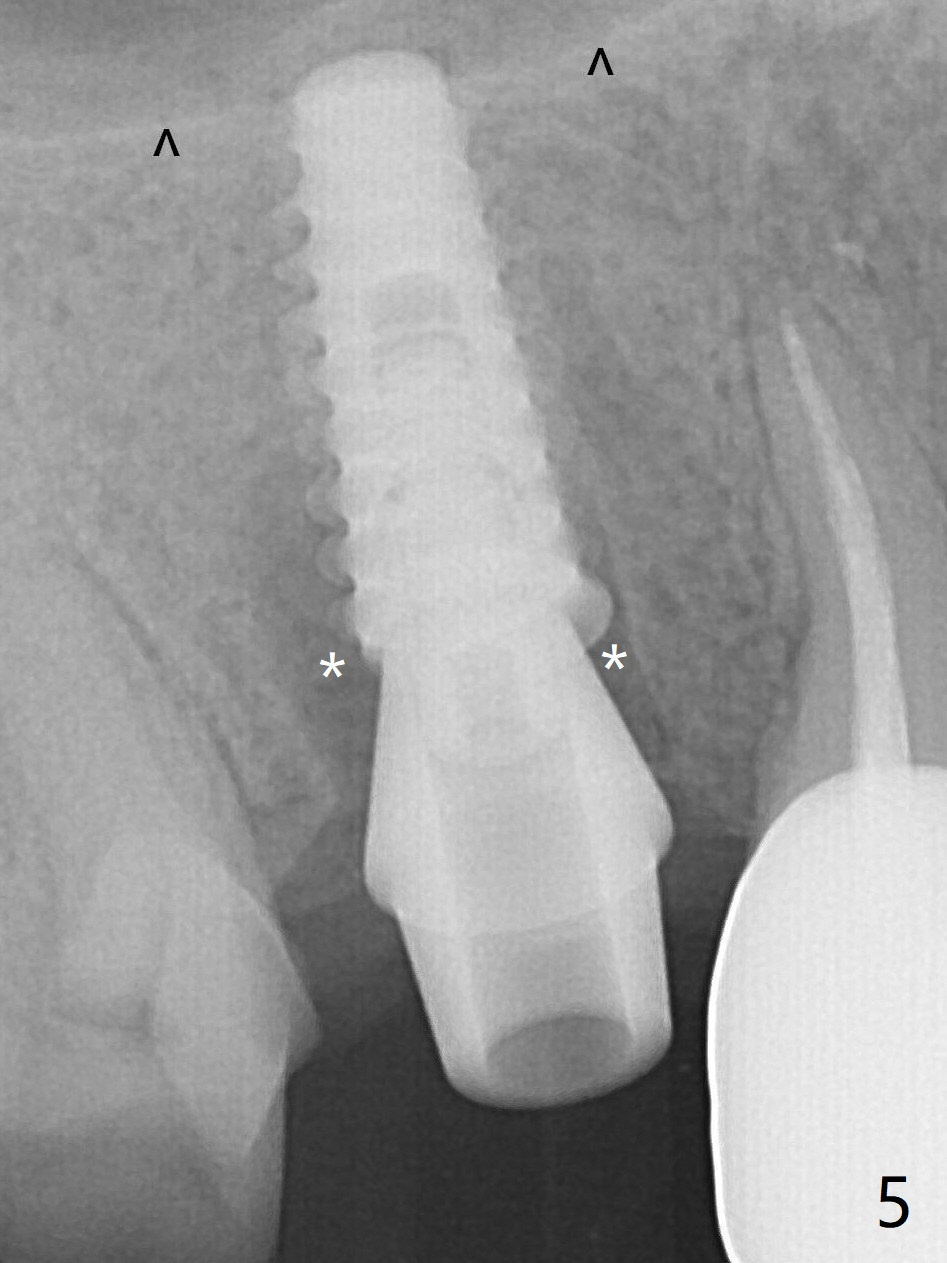

To reduce the gap and periimplantitis, a 5x11 mm IBS implant is placed with insertion torque > 50 Ncm after further osteotomy using Magic Drills (Fig.5). In fact the implant is placed too deep (as compared to Fig.3). Following placement of 5.5x4(4) mm abutment, a splinted provisional is fabricated at #3 and 4. An abutment with 5 or 6 mm cuff is needed. ^: sinus floor.

The peri-implant gaps (Fig.5 *) seem to disappear (Fig.6 (3 months postop)) with the help of bone graft.